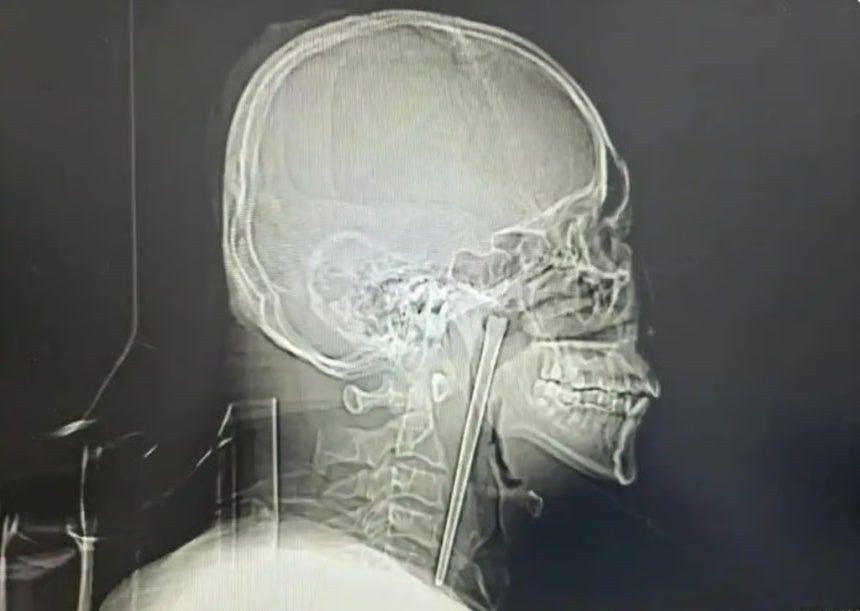

중국에서 한 남성이 길이 12㎝의 젓가락이 목에 박힌 채 8년을 버티다 제거 수술을 받았다. 사진 바이두 캡처

중국에서 한 남성이 길이 12㎝의 금속 젓가락이 목에 박힌 채 8년을 버티다 최근 제거 수술을 받아 눈길을 끌었다.

정밀 검사 결과 왕씨가 삼킨 젓가락은 목 안쪽 연구개 부위에 박혀 있었던 것으로 확인됐다. 의료진은 다행히 주변 점막에 손상이 없고 성대 기능 역시 정상적으로 유지되고 있었다고 설명했다.